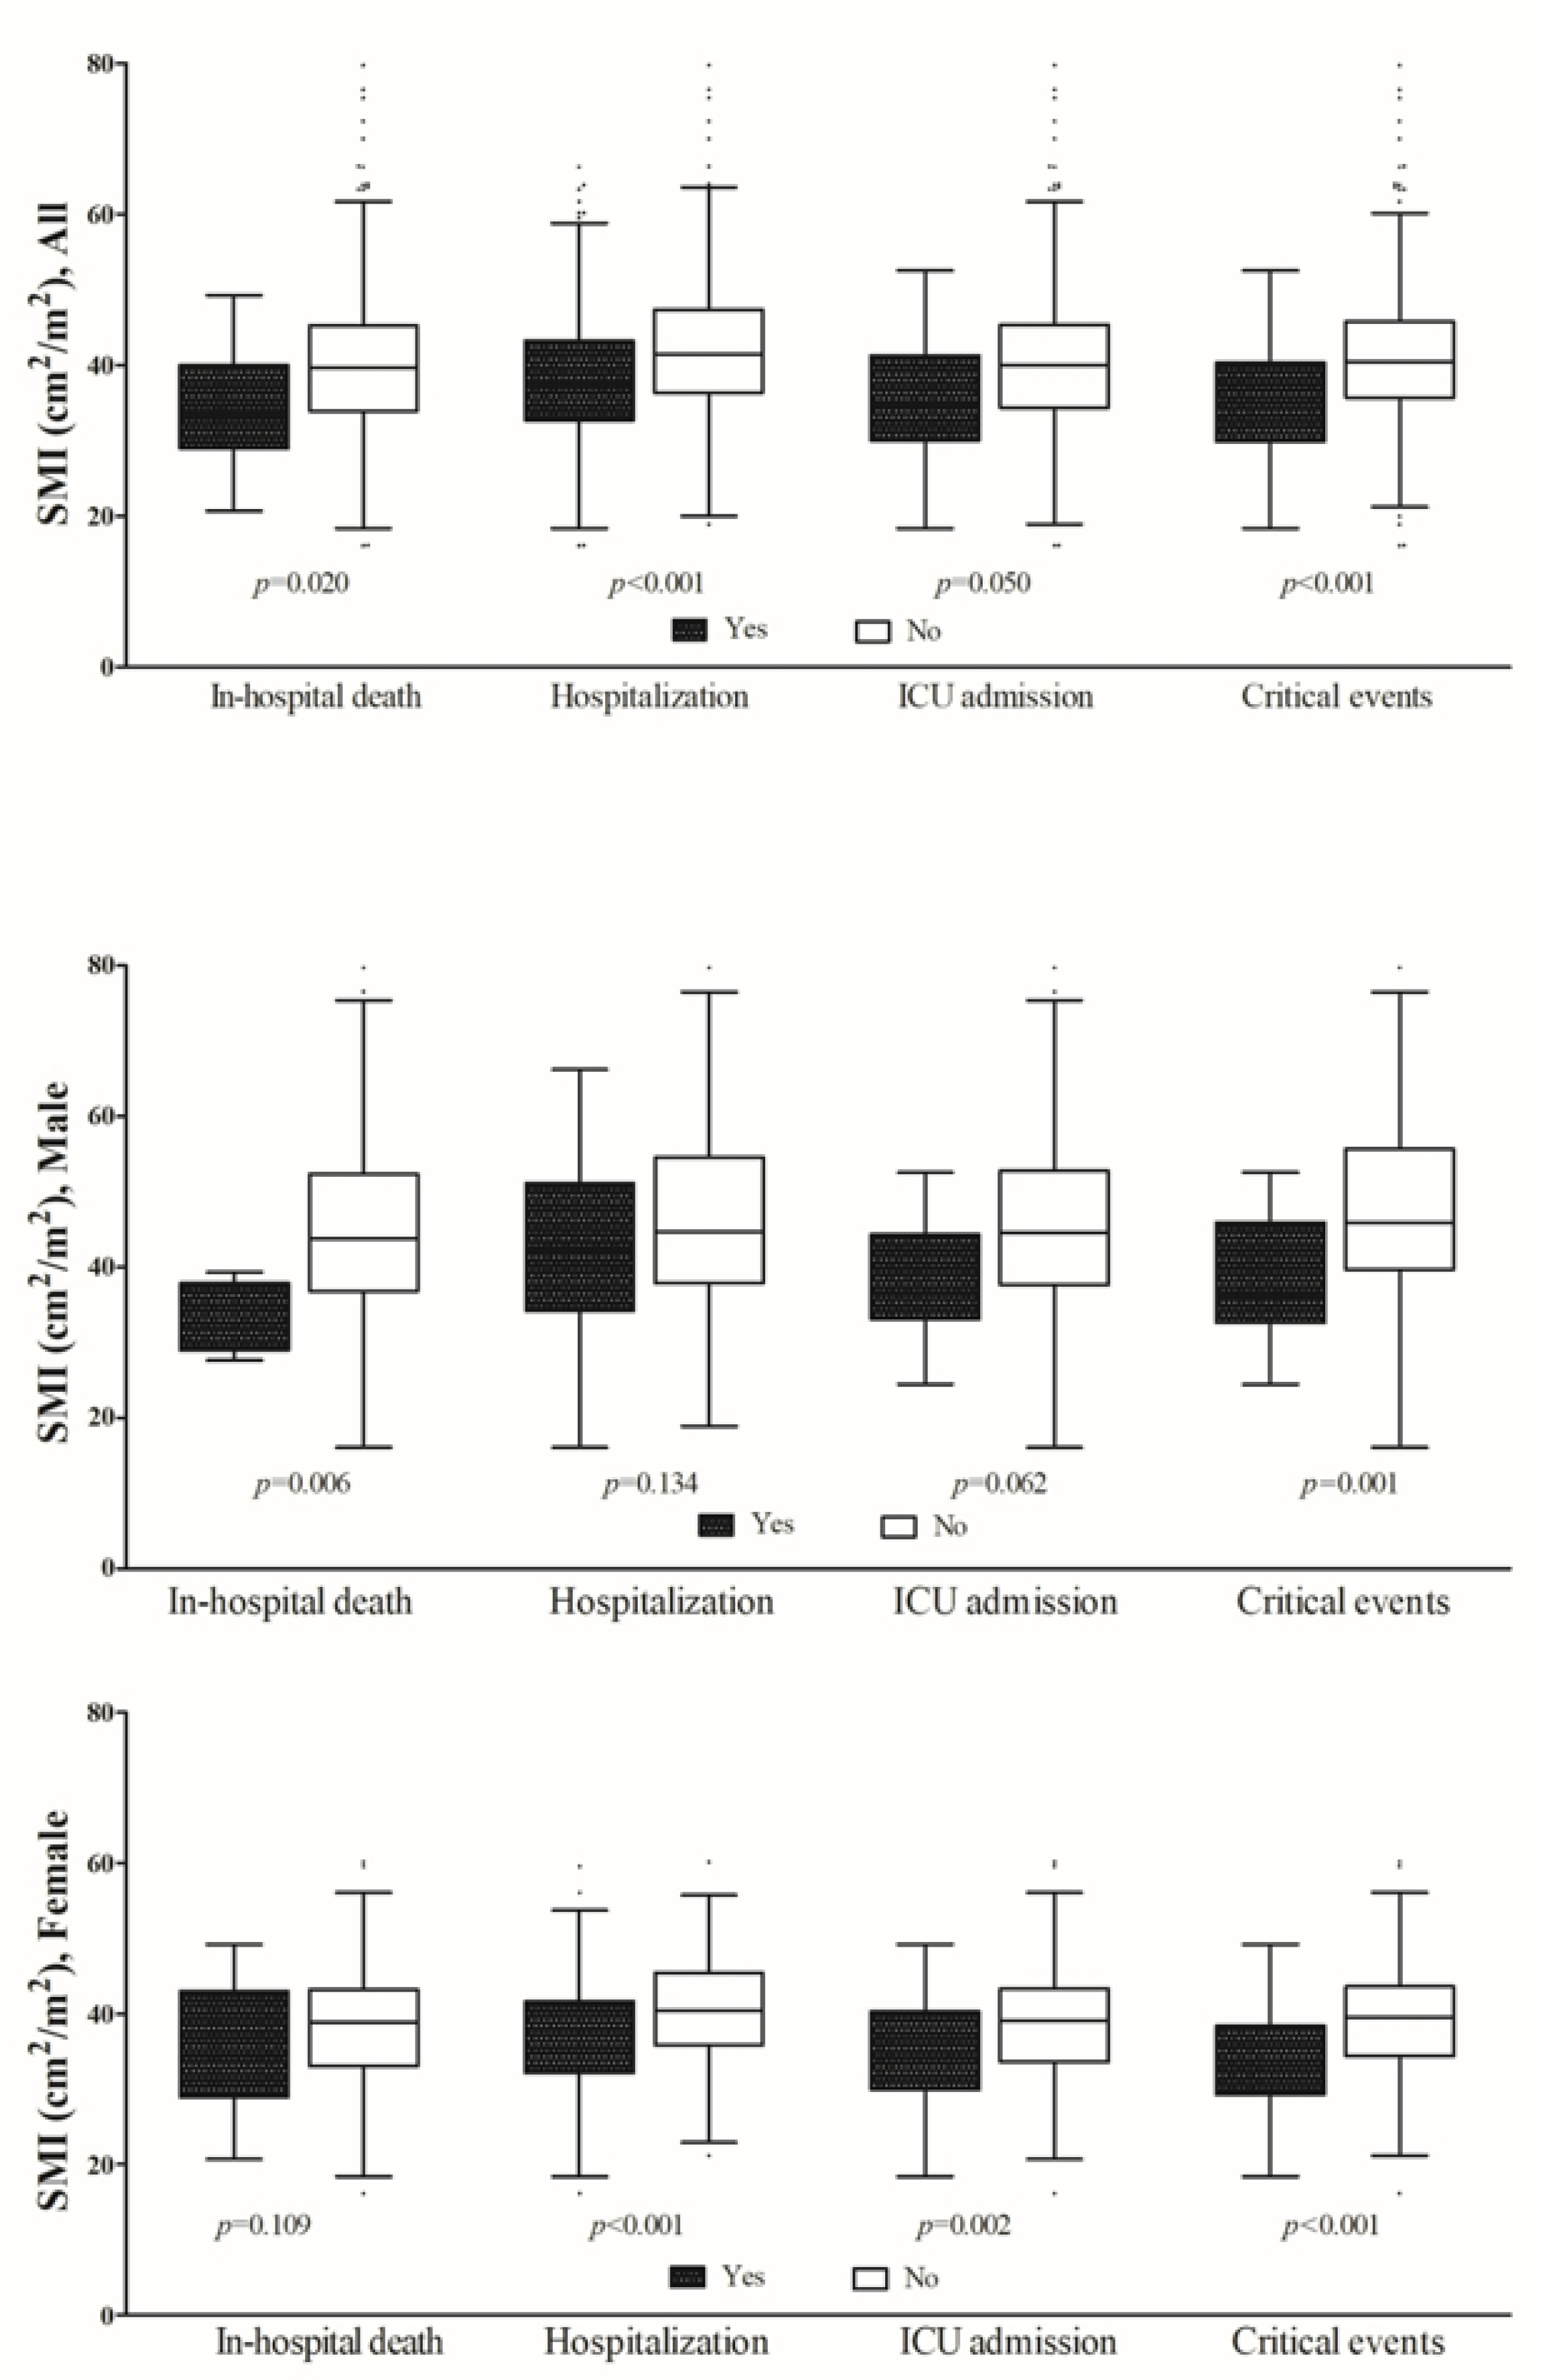

3.2. Clinical Outcomes

3.3. In-Hospital Mortality

3.4. Analysis for Predicting of Critical Events